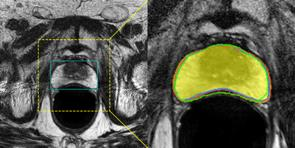

Accurate magnetic resonance imaging (MRI) segmentation is crucial for clinical decision-making, but remains labor-intensive when performed manually. Convolutional neural network (CNN)-based methods can be accurate and efficient, but often generalize poorly to MRI's variable contrast, intensity inhomogeneity, and protocols. Although the transformer-based Segment Anything Model (SAM) has demonstrated remarkable generalizability in natural images, existing adaptations often treat MRI as another imaging modality, overlooking these modality-specific challenges. We present SAMRI, an MRI-specialized SAM trained and validated on 1.1 million labeled MR slices spanning whole-body organs and pathologies. We demonstrate that SAM can be effectively adapted to MRI by simply fine-tuning its mask decoder using a two-stage strategy, reducing training time by 94% and trainable parameters by 96% versus full-model retraining. Across diverse MRI segmentation tasks, SAMRI achieves a mean Dice of 0.87, delivering state-of-the-art accuracy across anatomical regions and robust generalization on unseen structures, particularly small and clinically important structures.